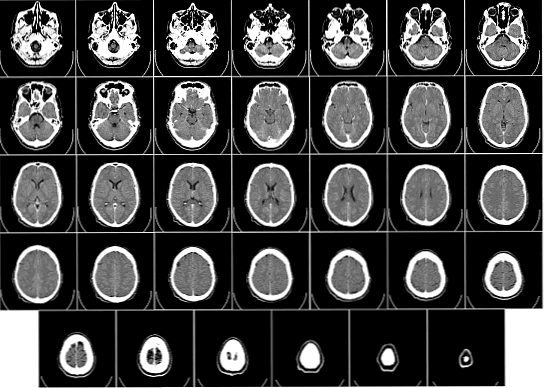

Кольпоцефалия - это тип порока развития головного мозга, который можно диагностировать еще до рождения, если можно доказать наличие увеличения затылочных рогов боковых желудочков.

Некоторые из диагностических методов, используемых при этой патологии: УЗИ, магнитно-резонансная томография, компьютерная томография, пневмоэнцефалография и вентрикулография.

Кольцецефалия является типом пороков развития головного мозга, который можно диагностировать до рождения, если можно продемонстрировать наличие увеличения затылочных рогов боковых желудочков (Gary et al., 1992).

Некоторые из диагностических методов, используемых в этой патологии: ультразвук ультразвуком, магнитный резонанс, компьютерная томография, пневмоэнцефалография и вентрикулография.

- Диагноз может быть сделан любым способом нейровизуализации: УЗИ, КТ или МРТ, включая пренатально.

Историческая справка и терминология

В 1940 году Бенда впервые признал «неудачу уменьшения размеров примитивных мозговых везикул» у умственно отсталого мальчика с эпилепсией и микроцефалией, у которых на невропатологическом обследовании также были отсутствовали мозолистые тела, микро- и макрогирия и гетеротопия серого вещества. Он использовал термин «везикулоцефалия» для этой желудочковой конфигурации (Benda 1940). В 1946 году Яковлев и Уодсворт обсуждали этого пациента как случай слизистой шизенцефалии и предложили вместо этого термин «колпоцефалия» (от греческого «кольпоса», что означает «пустота»), чтобы «избежать ошибочного кодирования латинских и греческих корней» (Яковлев и Уодсворт, 1946) ). Вначале колпоцефалия относилась к постоянным глобальным желудочкам (Barth et al., 1982). Позднее термин «колпоцефалия» ограничивался сохранением специфической формы конфигурации желудочков плода в постнатальной жизни, где затылочные рожки желудочков головного мозга остаются непропорционально большими и расширенными (Garg, 1982). Этот термин получил широкое признание и использовался с тех пор. Колонцефальная конфигурация желудочков в настоящее время наиболее легко распознается компьютерной томографией или магнитно-резонансной томографией головного мозга.

В прошлом пневмоэнцефалография или вентрикулография использовались с той же целью (Garg, 1982).